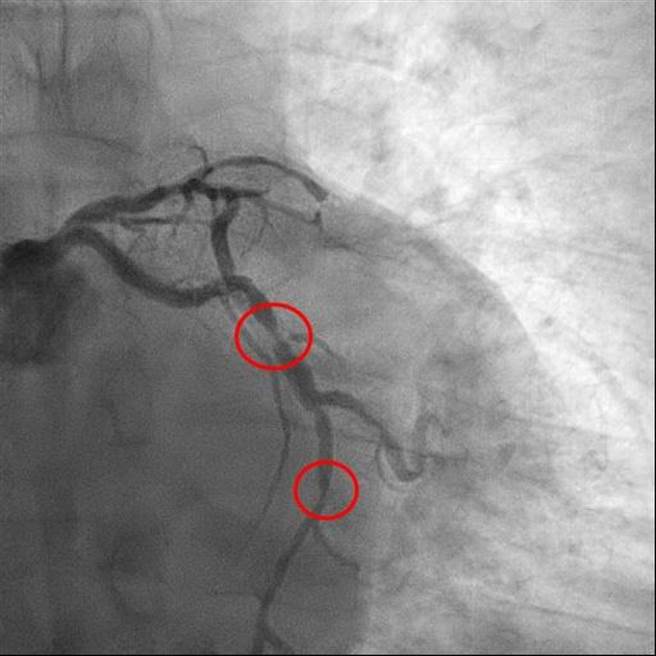

林男就医检查发现有3条冠状动脉严重钙化,经建议转院至亚大医院接受冠状动脉绕道手术治疗,半年来恢復情况不错,现在连续跑8公里路程还能脸不红、气不喘;而66岁的锺男不菸不酒,原本只有轻微高血压症状,9月开始却经常感到胸闷,就医检查发现3冠状动脉阻塞严重,手术后恢復正常。

亚洲大学附属医院心臟血管外科主任刘殷佐指出,冠状动脉主要供应心臟氧气与养分,若狭窄或阻塞,可能出现胸闷、气喘、心跳加速或头晕等情况,阻塞若未治疗,久了可能导致心肌梗塞。

刘殷佐表示,冠状动脉绕道手术是为阻塞的道路另辟一条高速公路,利用腿部大隐静脉或胸腔内壁内乳动脉的血管连接冠状动脉与主动脉,藉以让主动脉血流绕过阻塞处、到达未阻塞的冠状动脉部位,医院开院4年已执行逾百例开心手术。